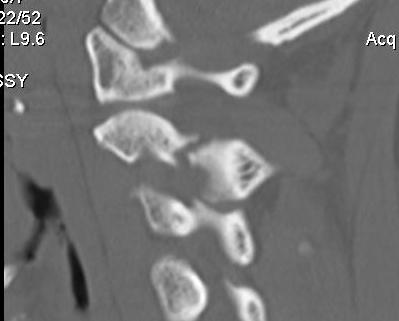

Bilateral pars fracture of C2

Traumatic spondylolisthesis of C2

CT scan